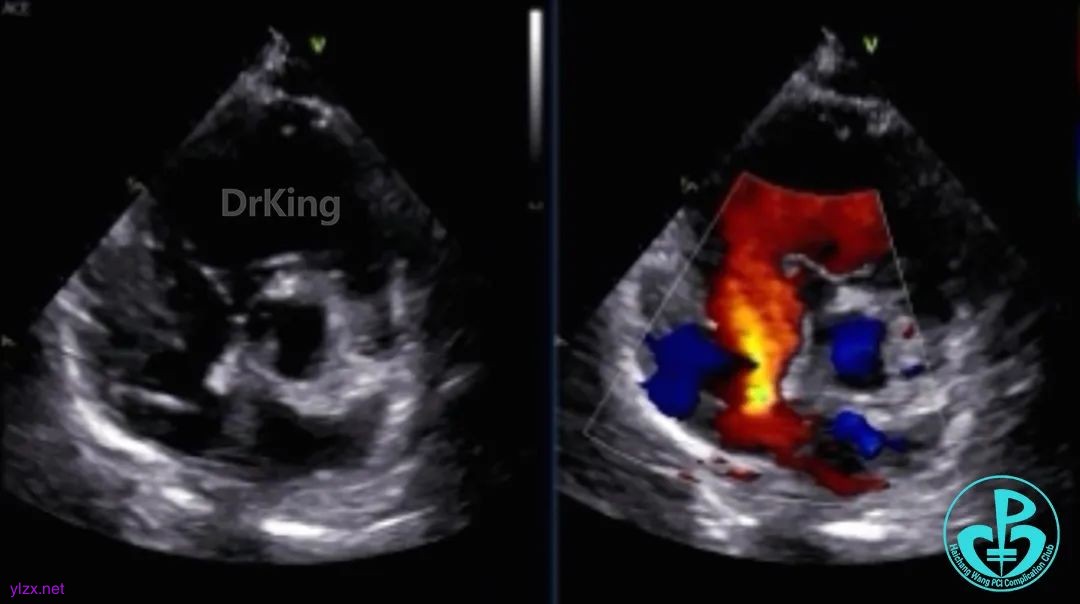

超声检查

房间隔中部有回声中断,测ASD大小:8×8×9mm,CDFI探及左向右分流,距主动脉根部0mm,距二尖瓣环10mm,距房顶14mm,距上腔静脉13mm,距下腔静脉11mm。

心脏彩超提示:先天性心脏病:房间隔缺(继发孔型)。右室稍增大。左心室收缩及舒张功能正常。右心室收缩功能正常。下腔静脉瓣冗长。

2. 本病例患者术前心脏彩超确诊为继发孔型房间隔缺损,缺损最大径达9mm,距主动脉0mm,距二尖瓣环10mm,距房顶14mm,距上腔静脉13mm,距下腔静脉11mm,存在左向右分流。术前检查显示右心室已出现代偿性增大,提示血流动力学异常持续存在,及时干预具有必要性,考虑到患者后续可能有房颤消融需求,谨慎沟通后患者主动选择使用可降解封堵器。